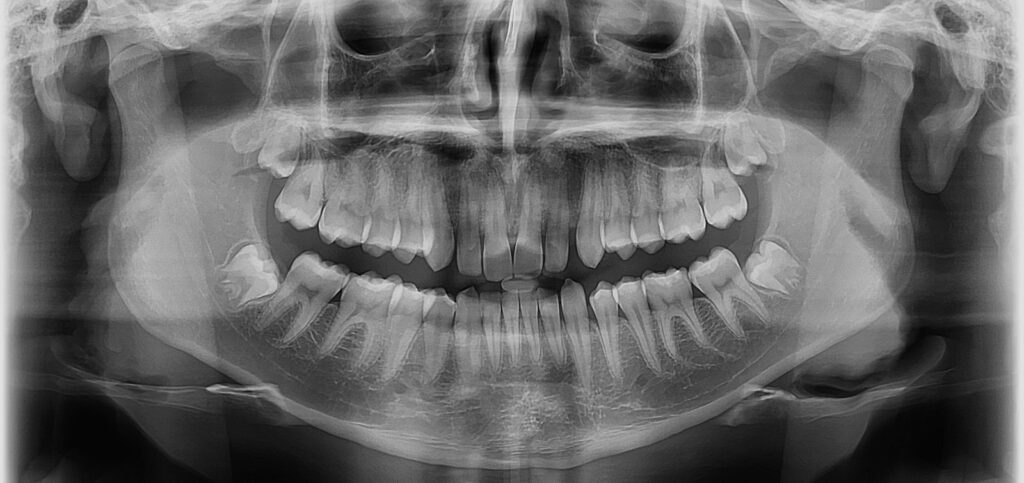

A radiografia panorâmica oferece uma visão abrangente da arcada dentária, maxilares e estruturas adjacentes em uma única imagem.

Detecção de cáries interproximais e lesões periodontais.

Avaliação de dentes inclusos e erupção dentária.

Planejamento para implantes dentários e extrações.

Identificação de anomalias ósseas e articulares.